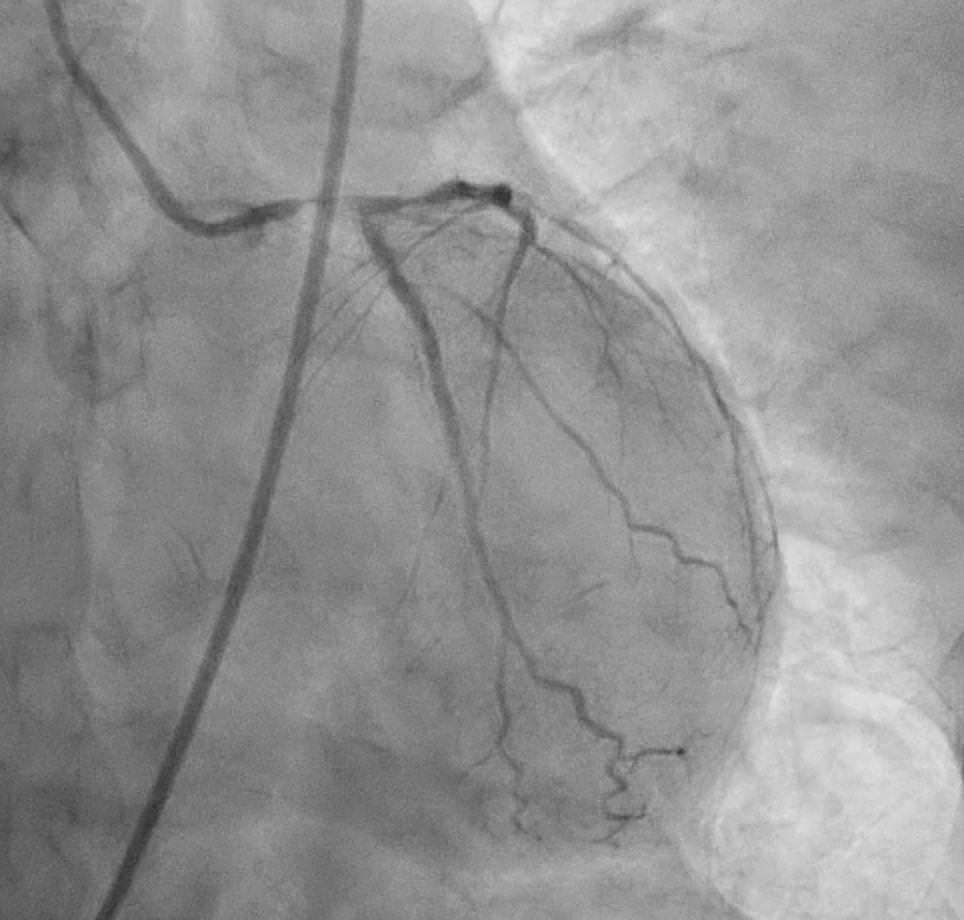

Severe CAD with LM + 3-vessel disease. dLM and shaft: critical stenosis; pLAD: critical stenosis; mLAD: s/p DES with stent underexpansion and proximal stent-edge restenosis; pLCX: s/p DES with proximal stent-edge restenosis; mRCA: 50% stenosis. SYNTAX score: 44.

Under IABP (left femoral), PCI via right brachial with 6 Fr EBU 3.5. Runthrough to LAD, Sion Blue to LCX. Predilation of LM/pLAD with 2.0¡¿20 mm balloon; IVUS pullbacks. Further dilatation with 2.5¡¿20 mm NC for mLAD underexpansion, pLAD, and LM. oLCX de novo and pLCX edge ISR predilated with 2.5¡¿20 mm NC; LCX ISR treated with DCB 2.5¡¿20 mm. Szabo technique attempted for LM–LAD with a 3.0¡¿24 mm DES; the undeployed stent dislodged during repositioning and was deployed at the dislodgement site. IVUS showed 2–3 struts protruding into the aorta from the LM ostium and incomplete pLAD coverage. Post-dilation with 3.5¡¿20 and 2.5¡¿20 mm NC; DCB 3.0¡¿20 mm for pLAD uncovered plaque and mLAD proximal edge ISR. Final CAG: TIMI 3 flow.At 3 months, staged PCI via right radial with 6 Fr EBU 3.5. Sion Blue ES to distal LAD. IVUS: mLAD stent underexpansion (MSA <2.0 mm©÷); wire not through struts. IVL 3.5¡¿12 mm initially could not cross LM; after guide exchange (JL 3.5, then EBU 3.0/3.5), IVL advanced to mLAD and delivered 100 shocks, producing a ring crack and area gain. Further dilation with 3.0¡¿20 and 3.5¡¿20 mm NC. IVUS: pLAD type B dissection without flow limitation. DCB 3.5¡¿40 mm to p–mLAD. LM ostial stent further dilated with 3.5¡¿20 mm. Final CAG: TIMI 3 flow.